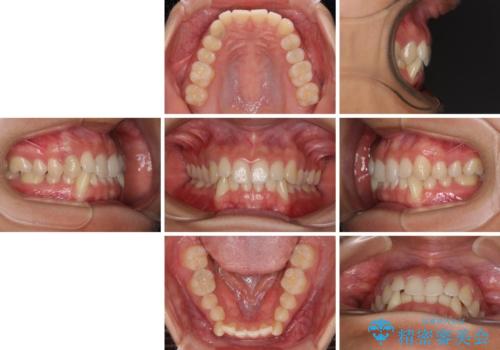

- 下顎の八重歯を気にして来院された患者様です。

マウスピース矯正でもワイヤー矯正でも対応可能であり、マウスピースによる治療を希望されたため、インビザラインを用いることとしました。

下顎前歯にデコボコが集中していたため、顎間ゴムによる後方移動とIPR(歯と歯の間を削ること)により歯列を整えることとしました。